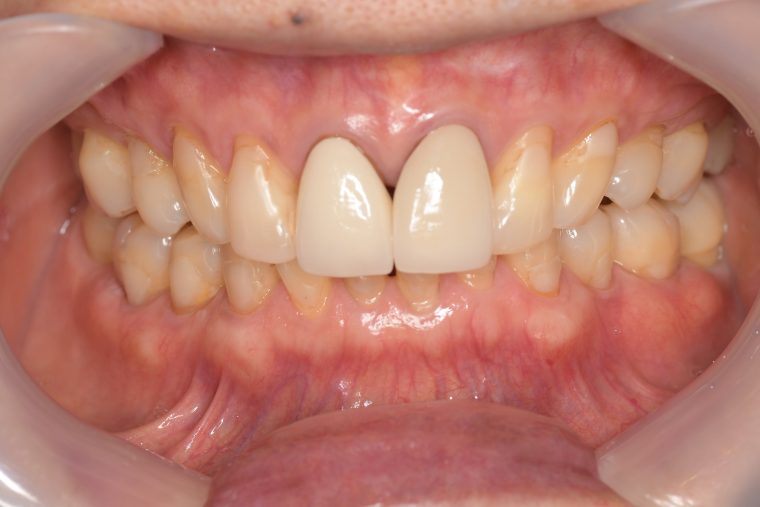

Before

症例

After

基本情報

年齢・性別 75歳・女性

主訴 主訴:左上奥の歯ぐきが腫れた

治療部位:左上下奥歯、右下奥歯

治療内容 1.歯周ポケット検査、歯磨き指導、抗生物質塗布

2.縁上の歯石除去

3.縁下の歯石除去

4.再評価

5.定期検診(3ヶ月おき)

→内容:口腔内写真、歯周ポケット検査、歯磨き指導、歯石除去、着色除去(PMTC)、フッ素塗布、ドクターによる虫歯のチェック、ナイトガードのチェック

治療期間 3ヶ月

治療費 定期検診の合計:3,210円(保険診療3割負担)

(2022年8月現在)

リスク・副作用 定期検診は個人によって期間を変えています。

ご自身での管理が困難な方や歯周病や虫歯のリスクが高い方は1ヶ月おきにクリーニングをしています。

その都度患者さまとご相談させて頂いた上で期間を決めさせて頂いています。

治療方針 1.歯周ポケット検査、歯磨き指導、抗生物質塗布

5.定期検診

特記事項 ・65年前に矯正治療をしてから歯をずっと大切にしてきたので、なるべく抜歯はしたくない。

・上の前歯は10年前にお孫さんがぶつかってきて、神経の治療をした。

・食いしばりをする癖がある為ナイトガード(夜間につける歯を保護するマウスピース)を作製し使用して頂いている。

担当者所見 左上は歯ぐきがかなり腫れていたが、歯石除去とホームケア(歯ブラシ、歯間ブラシSサイズ、ミクリンタフトブラシ)と抗生物質(軟膏)により腫れが落ち着いた。

それに加え、過度な力がかからないよう、ナイトガードを毎日使って頂くことと、日中の食いしばりにも気をつけてもらうようにした。

これは上の前歯を守るためのものでもあるので、必ず使用して頂いています。(上の前歯は神経がない為栄養が行き届かないので神経がある歯に比べ脆く根っこにヒビが入りやすい)

そして現在は定期検診で毎回異常がないか確認し、ホームケアではなかなか届かない歯周ポケット内のクリーニングを行っています。一度骨が溶けてしまっている為、歯周ポケットは残りますが、その後再発することは今のところなく、定期検診で今後もしっかり管理していきます。